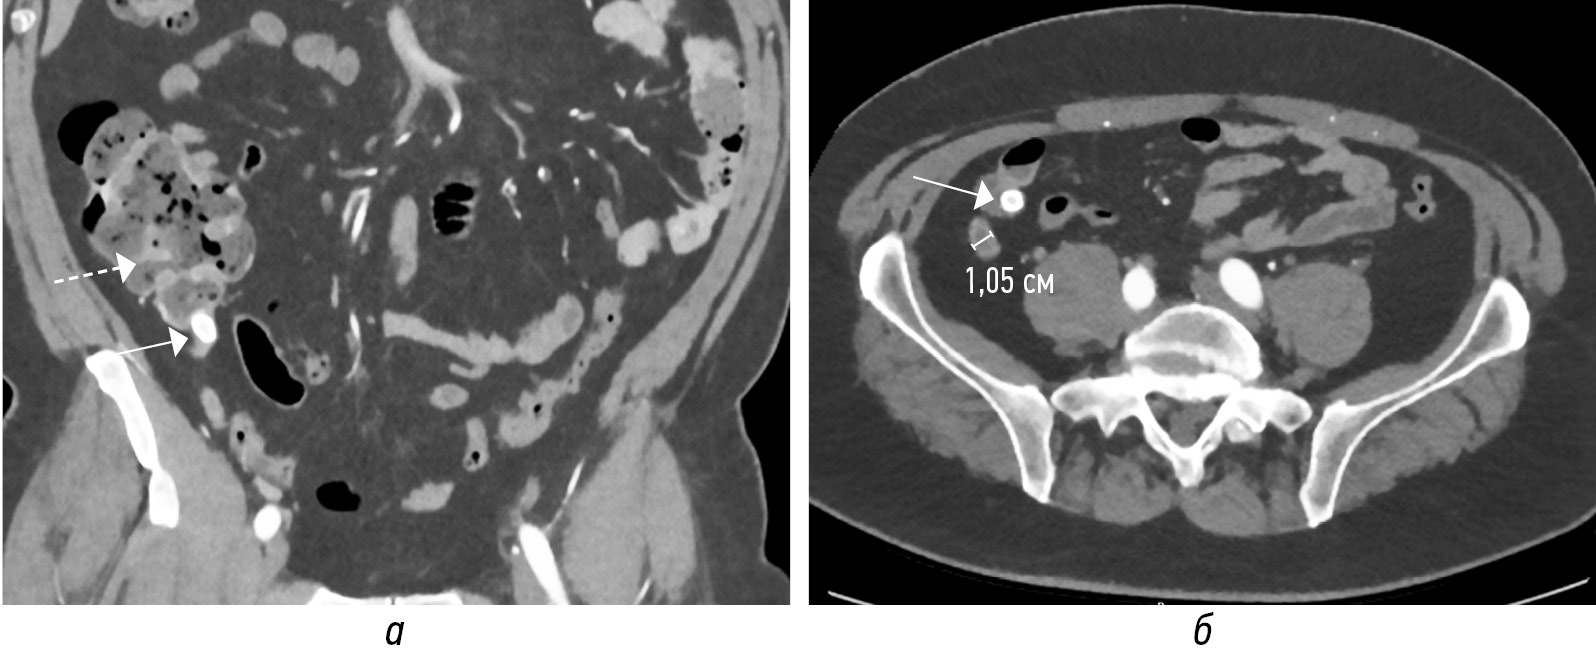

Просвет аппендикса может расширяться за счет неоднородного внутреннего содержимого без наличия (рис. 6, а, г) или с присутствием (рис. 6, б, в, д, е) аппендиколита. Другие косвенные признаки ОА: отек периаппендикулярной жировой клетчатки (рис. 7, а, б; 8, а, б); утолщение за счет отека прилежащей стенки кишки (рис. 9, а–г); расширение просвета кишки за счет газа иди жидкости с ослабленной перистальтикой; периаппендикулярное жидкостное скопление или абсцесс (рис. 10, а, б); лимфоаденопатия (рис. 11, а); абдоминальный выпот (рис. 11, г) [3, 16, 18].

Рис. 6. Сонограммы в В-режиме по длинной оси аппендиксов (а–в), КТ-изображения в аксиальной плоскости в нативную фазу (г–е) только с жидкостным содержимым в аппендиксе (а, г), с единичным аппендиколитом (б, д), с множественными аппендиколитами (в, е). Аппендиколиты указаны стрелками

Fig. 6. Sonograms in B-mode along the long axis of appendixes (а–в), CT images in the axial plane in the native phase (г–е) only with liquid contents in the appendix (а, г), with a single appendicolitis (б, д), with multiple appendicolitis (в, е). Appendicolites are indicated by arrows

Рис. 7. КТ-изображения во фронтальной (а) и в сагиттальной (б) плоскостях в нативную фазу: вокруг аппендикулярного отростка (стрелки) тяжистое уплотнение жировой клетчатки. Купол слепой кишки (пунктирная стрелка)

Fig. 7. CT images in the frontal (a) and sagittal (b) planes in the native phase: around the appendicular process (arrows) there is a heavy thickening of adipose tissue. Dome of the cecum (dotted arrow)

Рис. 8. Сонограммы в В-режиме (а — продольный скан аппендикса; б — поперечный скан аппендикса). Воспаленный аппендикс (стрелки) окружен воспаленной жировой тканью более высокой эхогенности

Fig. 8. B-mode sonograms (а — longitudinal scan of the appendix; б — transverse scan of the appendix). The inflamed appendix (arrows) is surrounded by inflamed adipose tissue of higher echogenicity

Рис. 9. На нативных КТ-томограммах в аксиальной (а) и фронтальной (б) плоскостях и соответствующих сонограммах (в, г) визуализируется аппендикс (стенки толщиной 4 мм, в просвете (до 6 мм) неоднородное содержимое) (стрелка) с отеком стенок слепой кишки (пунктирная стрелка). Прилежащая жировая клетчатка без видимых изменений

Fig. 9. On native CT-tomograms in the axial (а) and frontal (б) planes and corresponding sonograms (в, г), the appendix is visualized (walls 4 mm thick, in the lumen (up to 6 mm) heterogeneous contents) (arrow) with edema of the walls of the cecum (dotted arrow). Adjacent adipose tissue without visible changes

Рис. 10. На нативных КТ-томограммах в аксиальной плоскости визуализируется абсцесс (стрелка) с неразличимым на его фоне воспаленным аппендиксом. Купол слепой кишки (пунктирная стрелка)

Fig. 10. On native CT scans, an abscess (arrow) is visualized in the axial plane with an inflamed appendix indistinguishable against its background. Dome of the cecum (dotted arrow)

Рис. 11. Нативные КТ-томограммы в аксиальной плоскости. Острый аппендицит с реактивной регионарной лимфоаденопатией (а, стрелка), отеком прилежащей жировой клетчатки (б, стрелка), с наличием аппендиколитов (в, стрелки), утолщением стенок слепой кишки (в, пунктирная стрелка), малого абдоминального выпота (г, стрелка)

Fig. 11. Native CT-tomograms in the axial plane. Acute appendicitis with reactive regional lymphadenopathy (а, arrow), edema of the adjacent adipose tissue (б, arrow), with the presence of appendicolitis (в, arrow), thickening of the walls of the cecum (в, dotted arrow), small abdominal effusion (г, arrow)